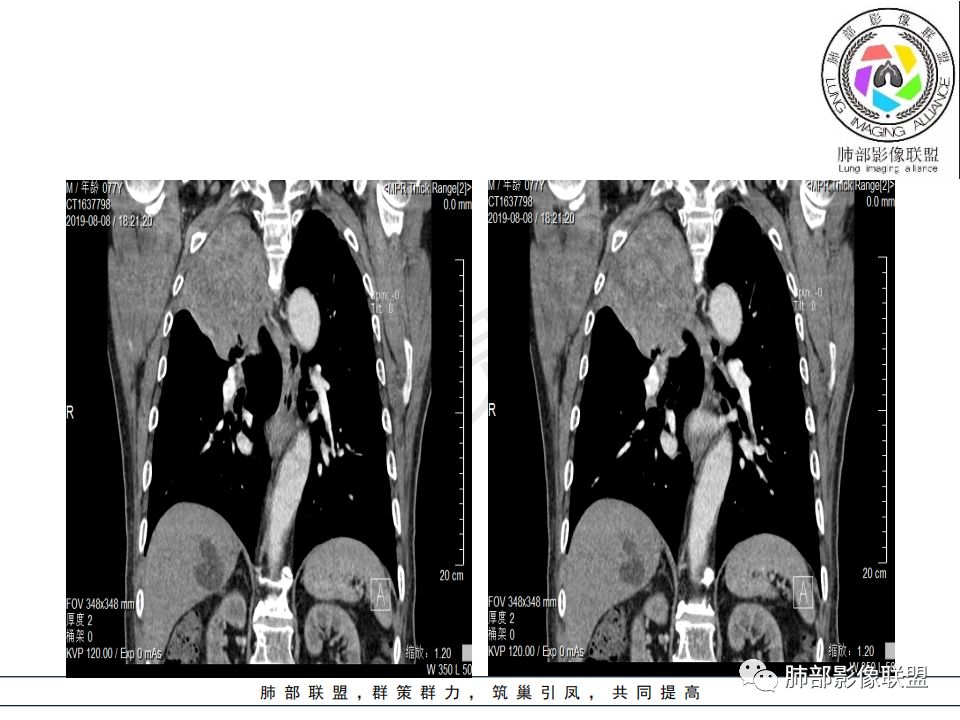

影像:影像右侧大支气管阻塞,临床没有症状或很轻微,要想到胃腺癌转移;胸壁代偿好,透亮度稍低不明显,慢性过程;34.8-52.5HU,主病灶支气管前壁另有1结节,都做成增强两期了,动脉期较平扫有强化;

尘缘:

从强化情况和冠状位看主要还是从外向内的一个肿块,有不张,但不张范围不大,近端支气管堵塞,考虑腺癌或类癌(原发或转移都可能),鉴别鳞癌。

@刘鋆(福州长乐区医院)影像科 转移啊,腔外都在生长,部分通过支气管壁进入腔内

@刘鋆(福州长乐区医院)影像科 先转移生长到外面,然后进入腔内生长,也是外朝内一种,与平时那种外朝内生长逐渐侵犯近端气管没有太多区别,只不过这个是转移而已。